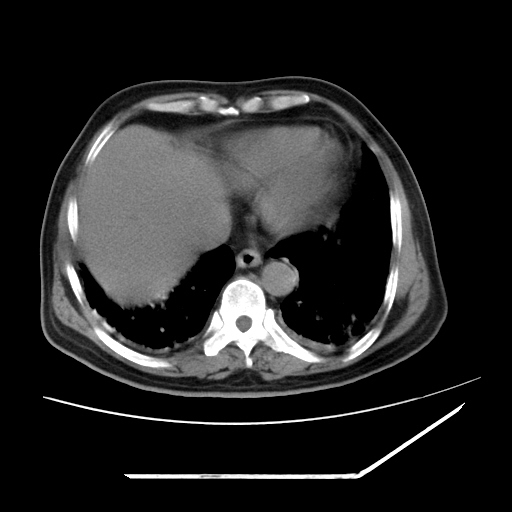

男,57,畏寒,发热

两肺野多发大小不一高密度灶,纵膈内见肿大淋巴结,要考虑转移瘤可能。双侧胸腔少量积液。

1)考虑两肺感染性病变(金黄色葡萄球菌肺炎?);建议抗炎治疗后复查排除其他。2)双侧少量胸腔积液。